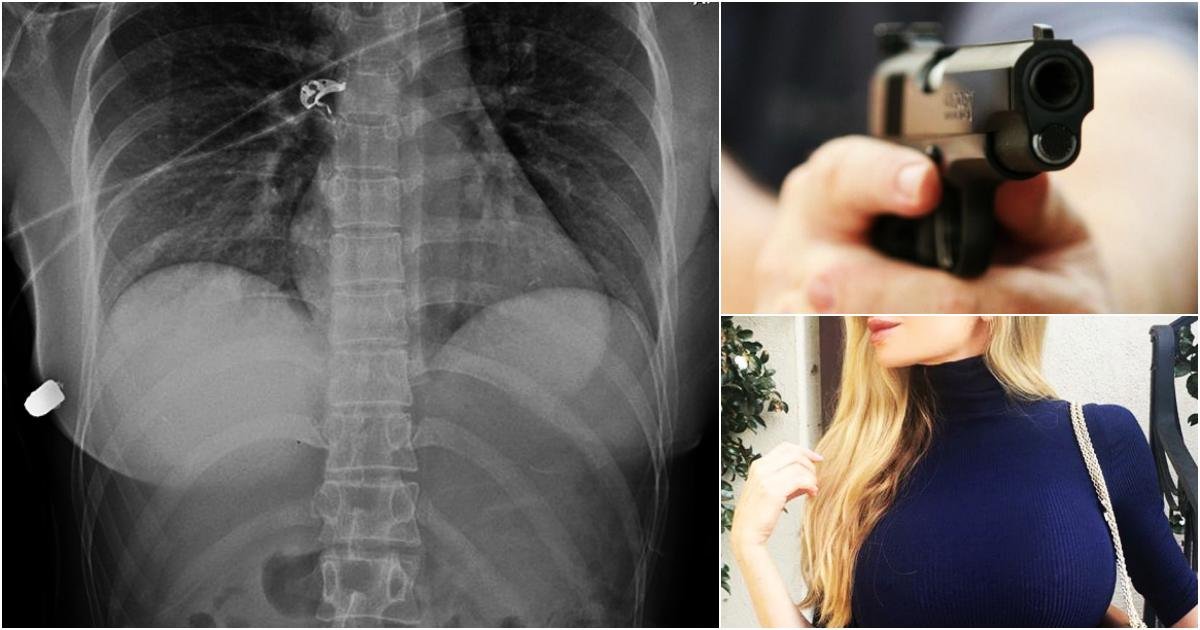

As the operation goes, medics found a hard, bullet-like object in the woman’s right lower anterior thoracic wall below the right breast.

Using trauma radiographs, medical experts were able to find the bullet in the right lateral thoracic wall, a fractured rib and air bubbles in the left breast, and concluded that the bullet traveled from the left breast to the right thoracic wall.